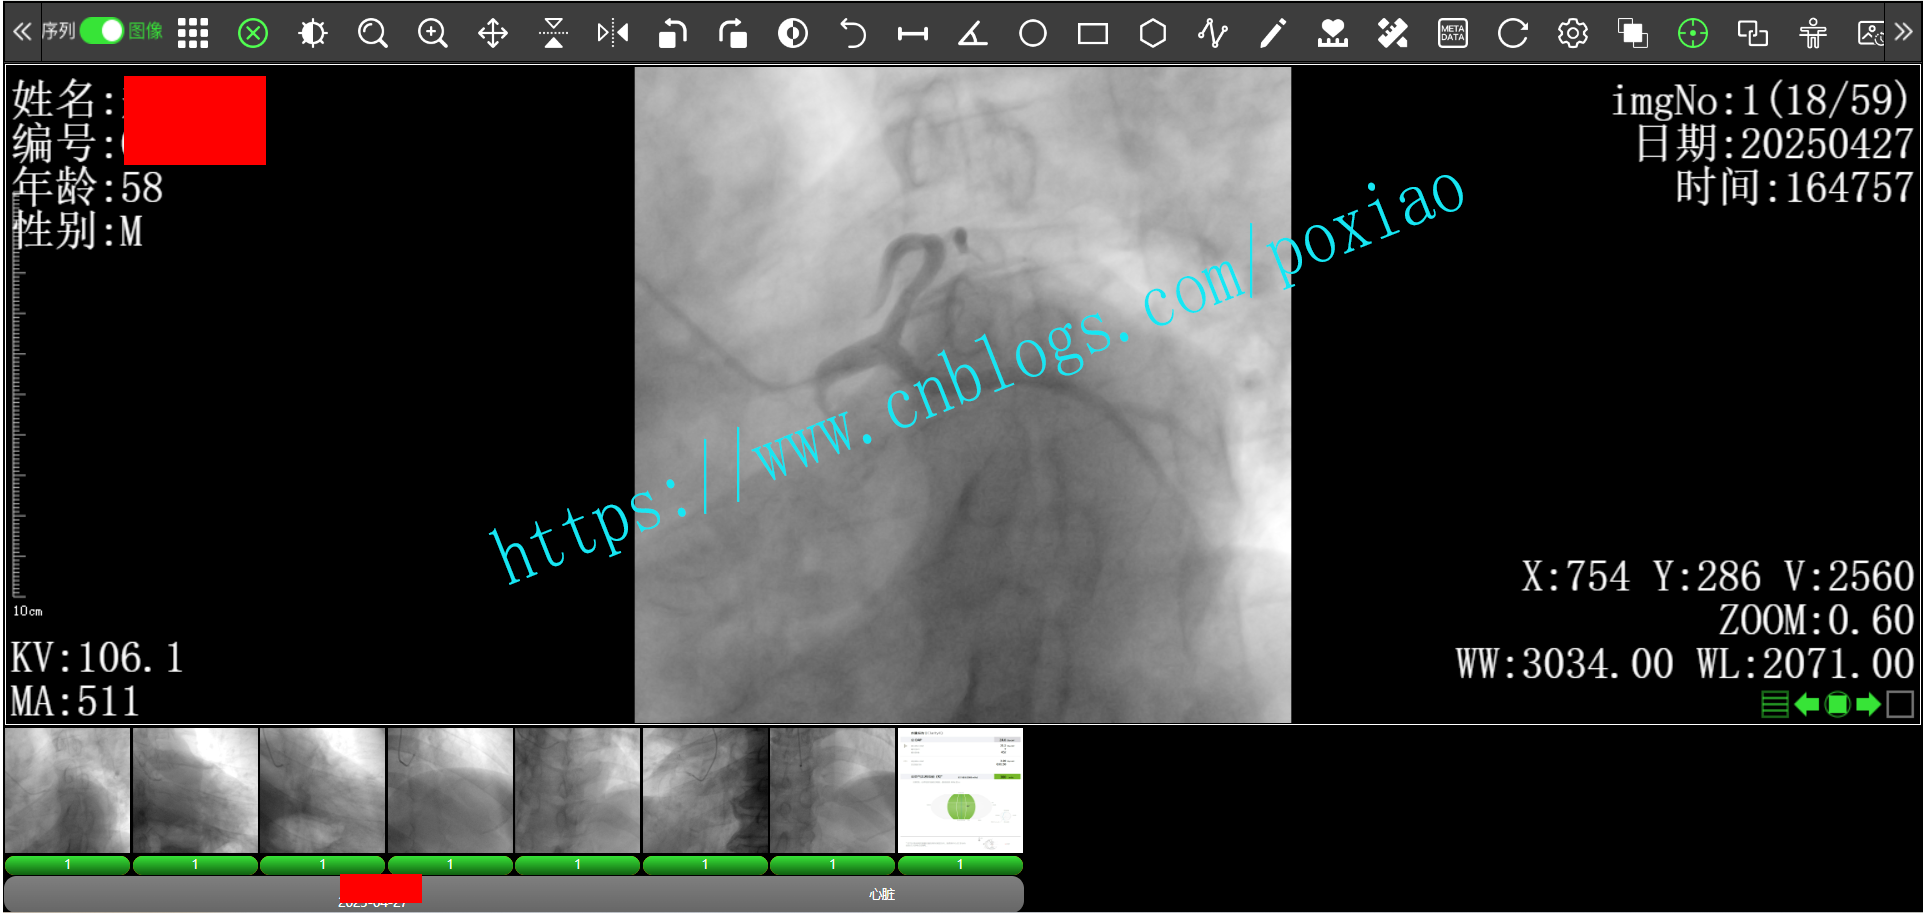

6.支持DSA等多帧图像的加载和播放功能.